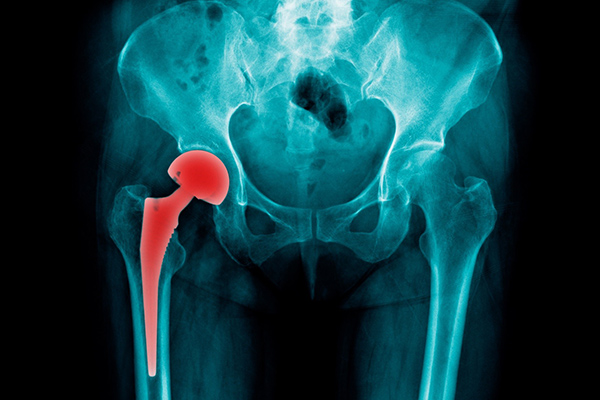

ผู้ป่วยโรคข้อเสื่อมส่วนใหญ่มักกังวลและไม่มั่นใจผลจากการผ่าตัดเปลี่ยนข้อเทียม เช่น กลัวความเจ็บปวด การกลับมาใช้ชีวิตประจำวันได้ตามปกติหรือไม่ จึงทนอยู่กับอาการเจ็บปวดที่ทรมาน คลินิกผ่าตัดเปลี่ยนข้อเทียม โรงพยาบาลซีจีเอช เข้าใจทุกความรู้สึกของผู้ป่วย จึงพร้อมให้บริการผ่าตัดเปลี่ยนข้อเทียมโดยคณะแพทย์และบุคลากรทางการแพทย์สหสาขาที่มีความเชี่ยวชาญเฉพาะทาง ด้วยเครื่องมือและเทคโนโลยีทางการแพทย์ที่ทันสมัย โดยเน้นมาตรฐานการรักษาระดับสากล ตั้งแต่การลงทะเบียนซักประวัติผู้ป่วยไปจนถึงการติดตามผลการรักษาหลังผ่าตัด เพื่อเป้าหมายสูงสุดคือ ให้ผู้ป่วยหายจากการเจ็บปวด สามารถกลับไปใช้ชีวิตประจำวันมีอายุการใช้งานของข้อเทียมที่ยืนนานและมีคุณภาพชีวิตที่ดีดังเดิม

ภาวะข้อเสื่อม จากการใช้งานหนัก อายุมากขึ้น โรคไขข้ออักเสบ โรครูมาตอยด์ ผู้ป่วยมักมีอาการปวดข้อมาก ข้อผิดรูปหรือมีการโก่งของข้อ ผู้ป่วยไม่ตอบสนองต่อการรักษาทั่วไปที่ไม่ใช่การผ่าตัด เช่น การรับประทานยา การทำกายภาพบำบัดและการลดน้ำหนัก